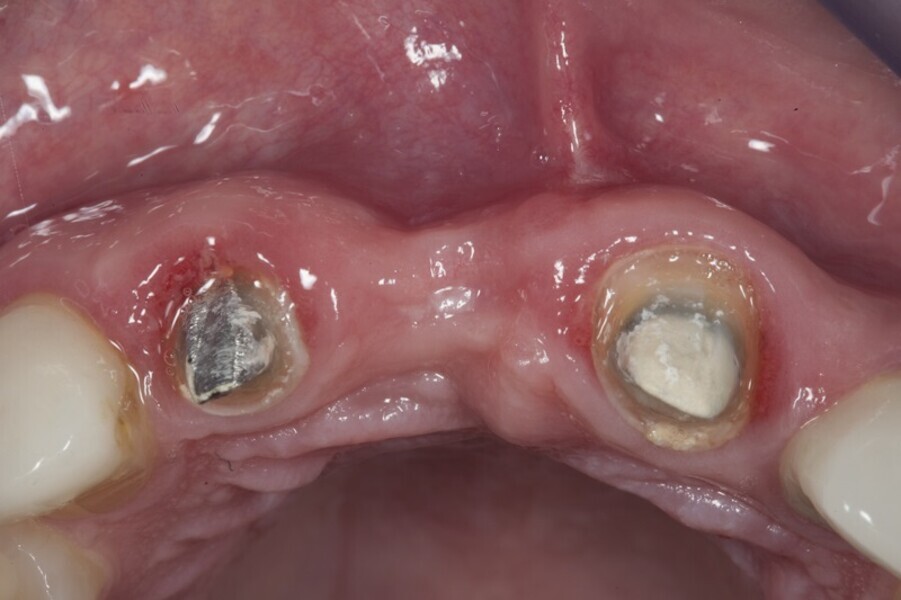

Biomodulacja laserem Nd:YAG z użyciem głowicy Genova®